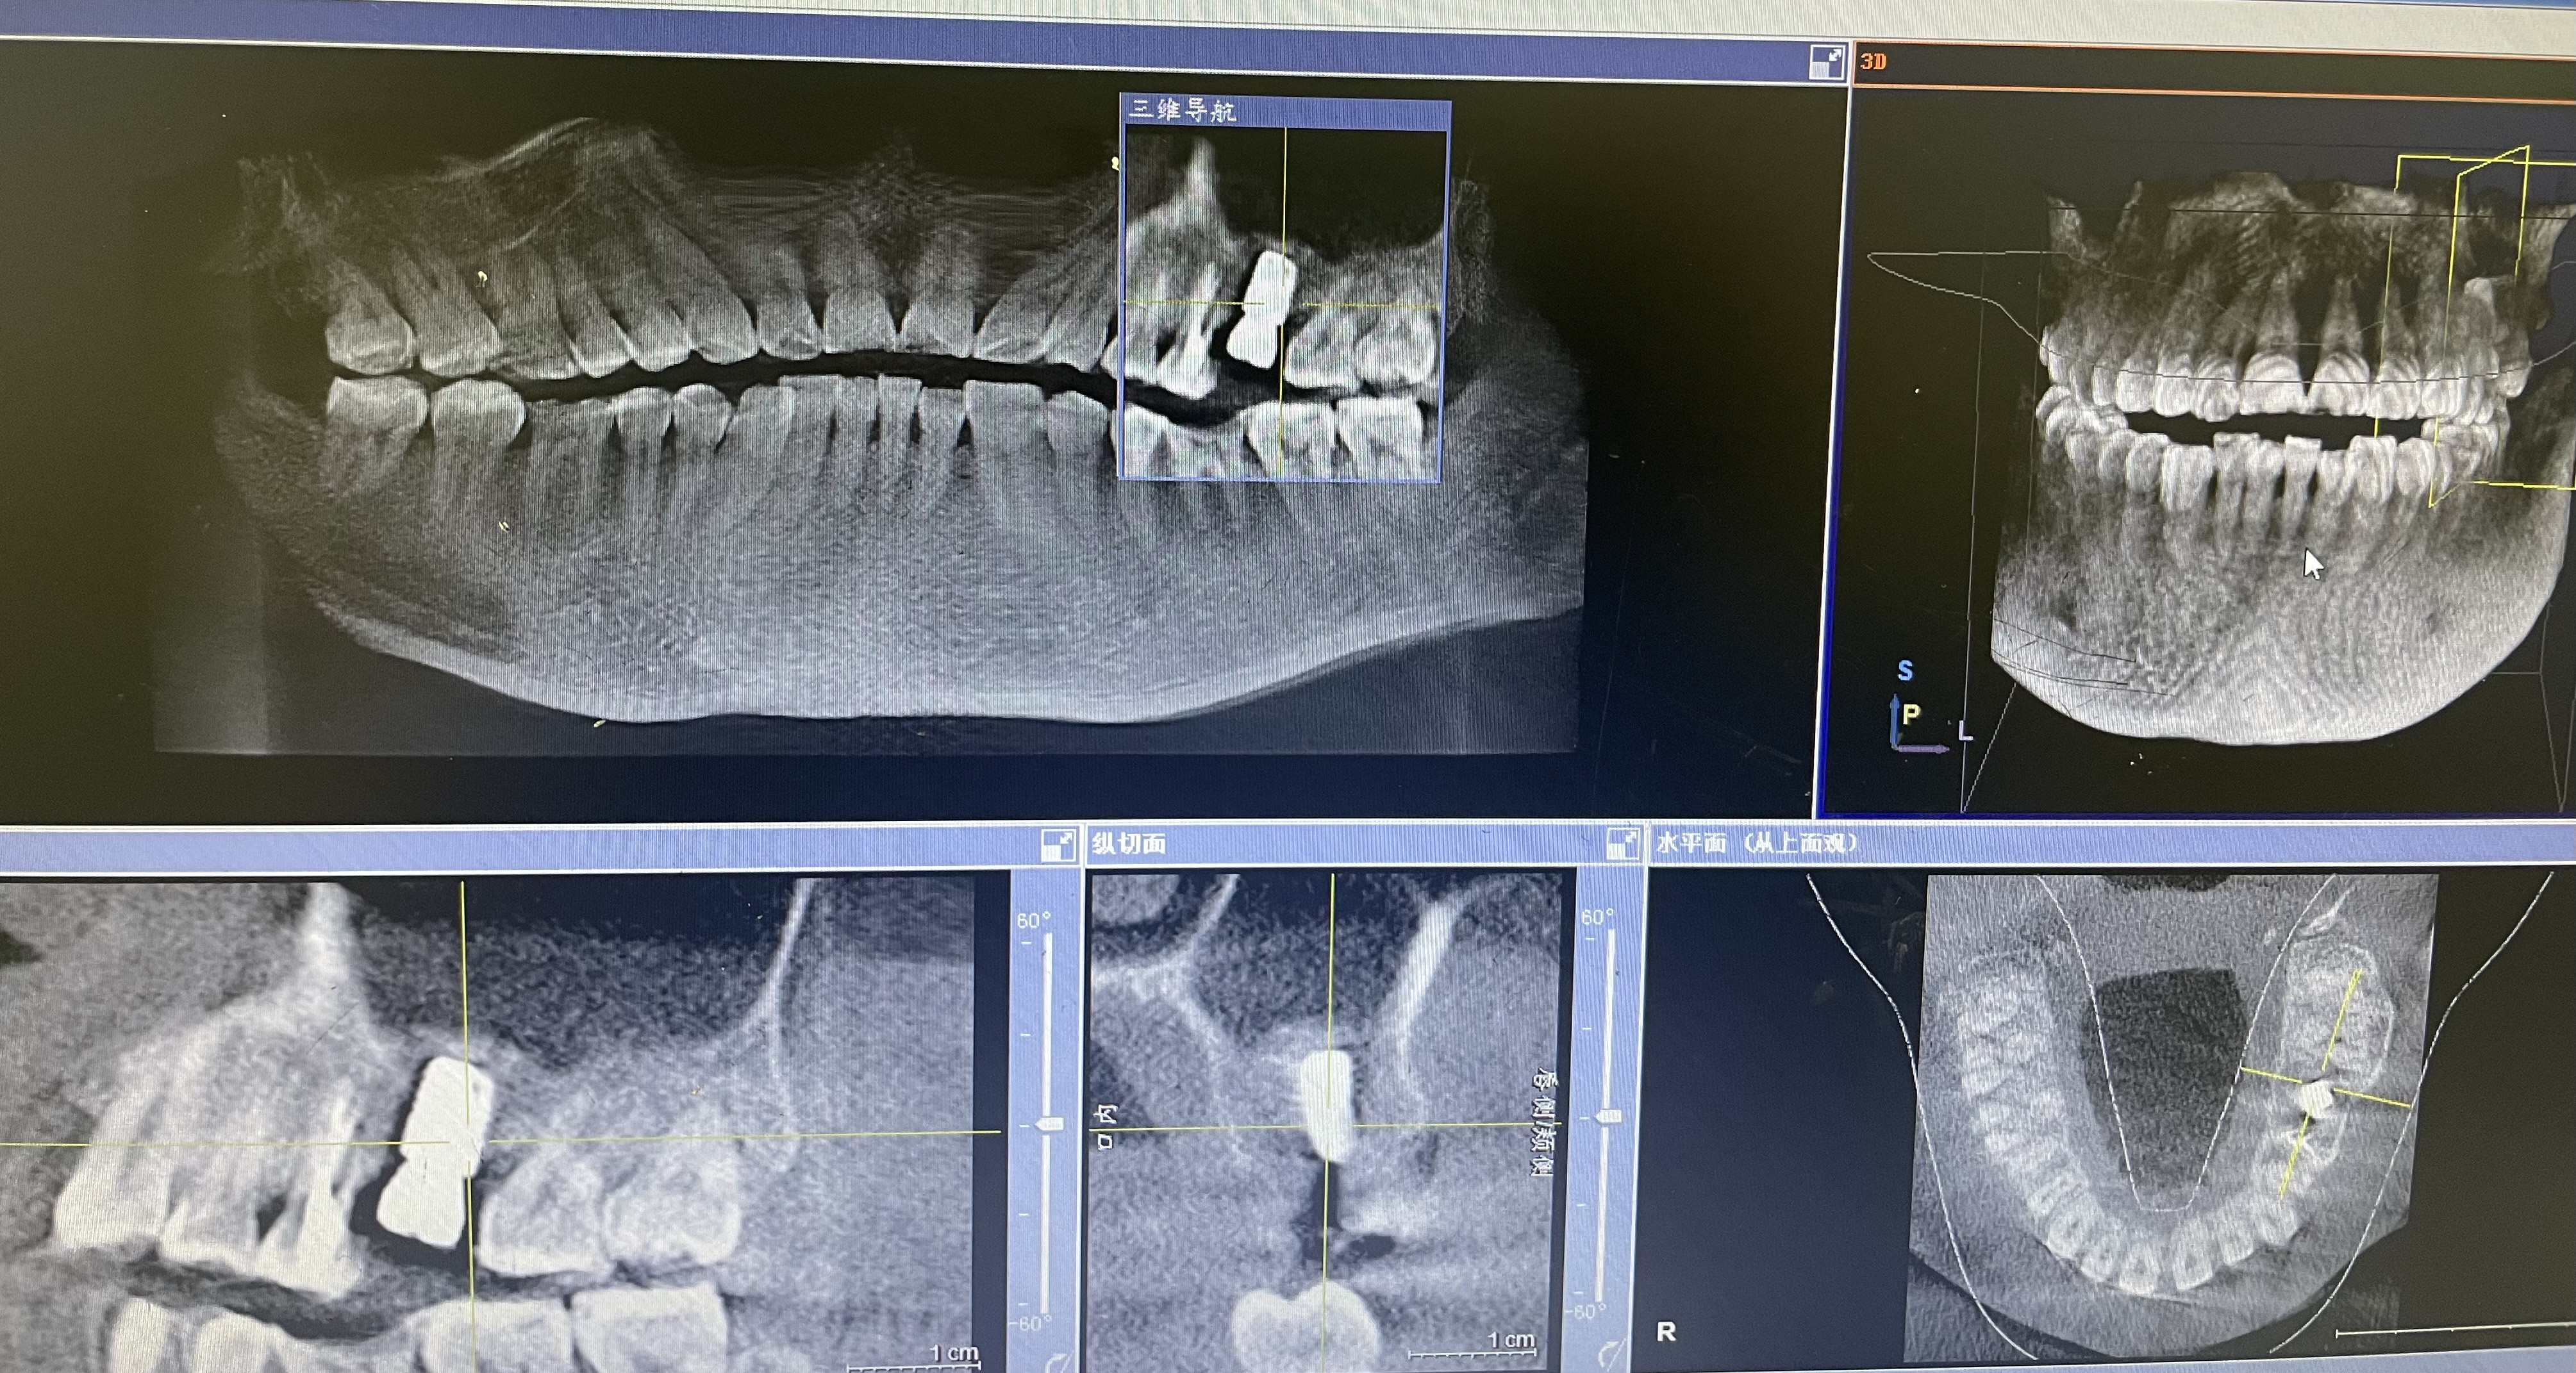

一口好牙是许多老年人幸福生活的保障,然而潘大伯(化名)却在种牙之路上历经波折。潘大伯多颗牙齿缺失,这给他的饮食和生活都带来了极大不便,种牙成为他心心念念的愿望。 他先后辗转于多个医院的口腔科,可均被告知牙槽骨条..